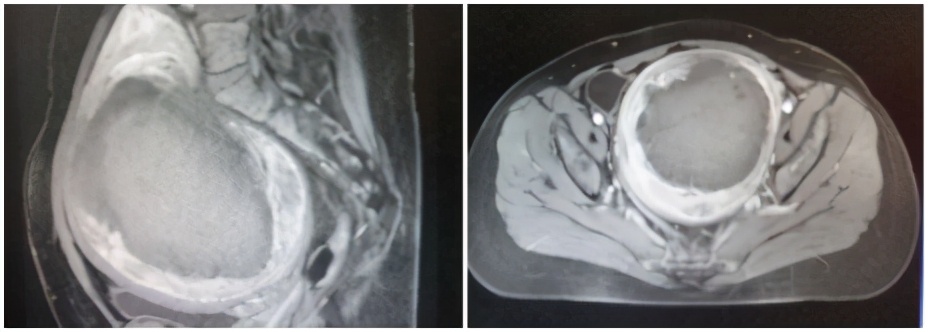

事实:应用海扶刀®设备治疗子宫肌瘤对于肌瘤的大小没有特别的限制,只要海扶刀®机载超声定位能够看得见的、能够建立安全超声治疗通道的,通常都能够进行消融治疗。几公分,十几公分,甚至二十几公分的肌瘤海扶刀®设备都可以治疗,并且一般是一次性消融治疗,只有极少数肌瘤特别大的情况可能需要分次消融治疗。

(子宫肌瘤145*120*102mm,应用海扶刀®设备一次性消融治疗)